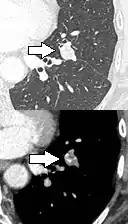

CT scan

For incidentally detected nodules on CT scan, Fleischner Society guidelines are given in table below. For multiple nodes, management is based on the most suspicious node.[8] These guidelines do not apply in lung cancer screening, in patients with immunosuppression, or in patients with known primary cancer.[8]